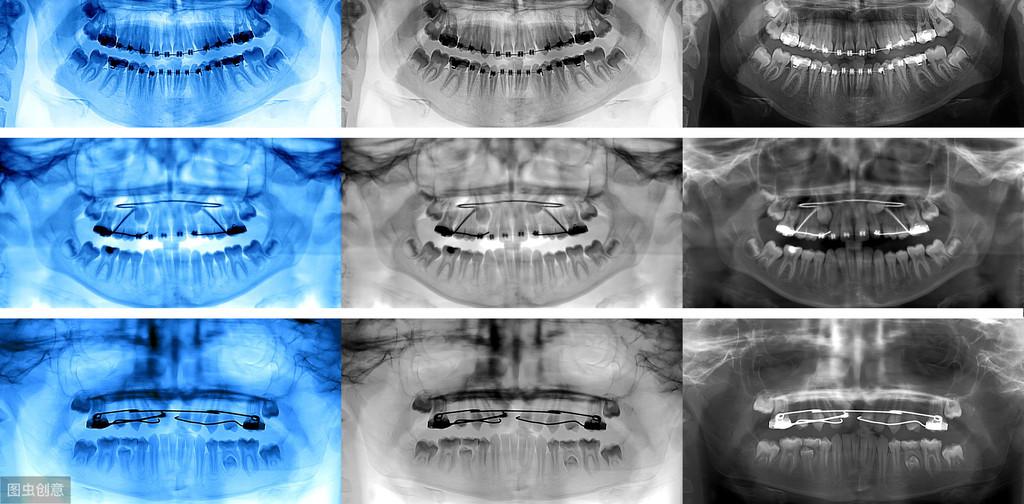

牙齒種植術(shù)是目前好的缺失牙齒修復(fù)技術(shù)之一,因?yàn)樗姆N植技術(shù)是通過(guò)手術(shù)將種植體植入到牙槽骨里,獲得了骨組織的固位支持,所以種植牙齒的穩(wěn)定性、性和使用年限都高,因此,種植牙從發(fā)展到現(xiàn)在也獲得了醫(yī)學(xué)界專家廣泛的認(rèn)可和大量有需要患者的喜愛(ài)。

也正是因?yàn)樾枰ㄟ^(guò)手術(shù)的方法將種植體植入到牙槽骨里,所以也會(huì)有部分患者會(huì)心存顧慮,針對(duì)這些備受關(guān)注的問(wèn)題,我們今天就來(lái)好好的聊一下;

我是牙科醫(yī)生黃征難,36年從業(yè)經(jīng)歷,如果你有任何口腔問(wèn)題,歡迎關(guān)注后在主頁(yè)私信咨詢,或評(píng)論留言!可以私信牙片,我來(lái)幫你免費(fèi)問(wèn)診!拓展知識(shí):瑞士種植牙系統(tǒng)多少錢一個(gè)